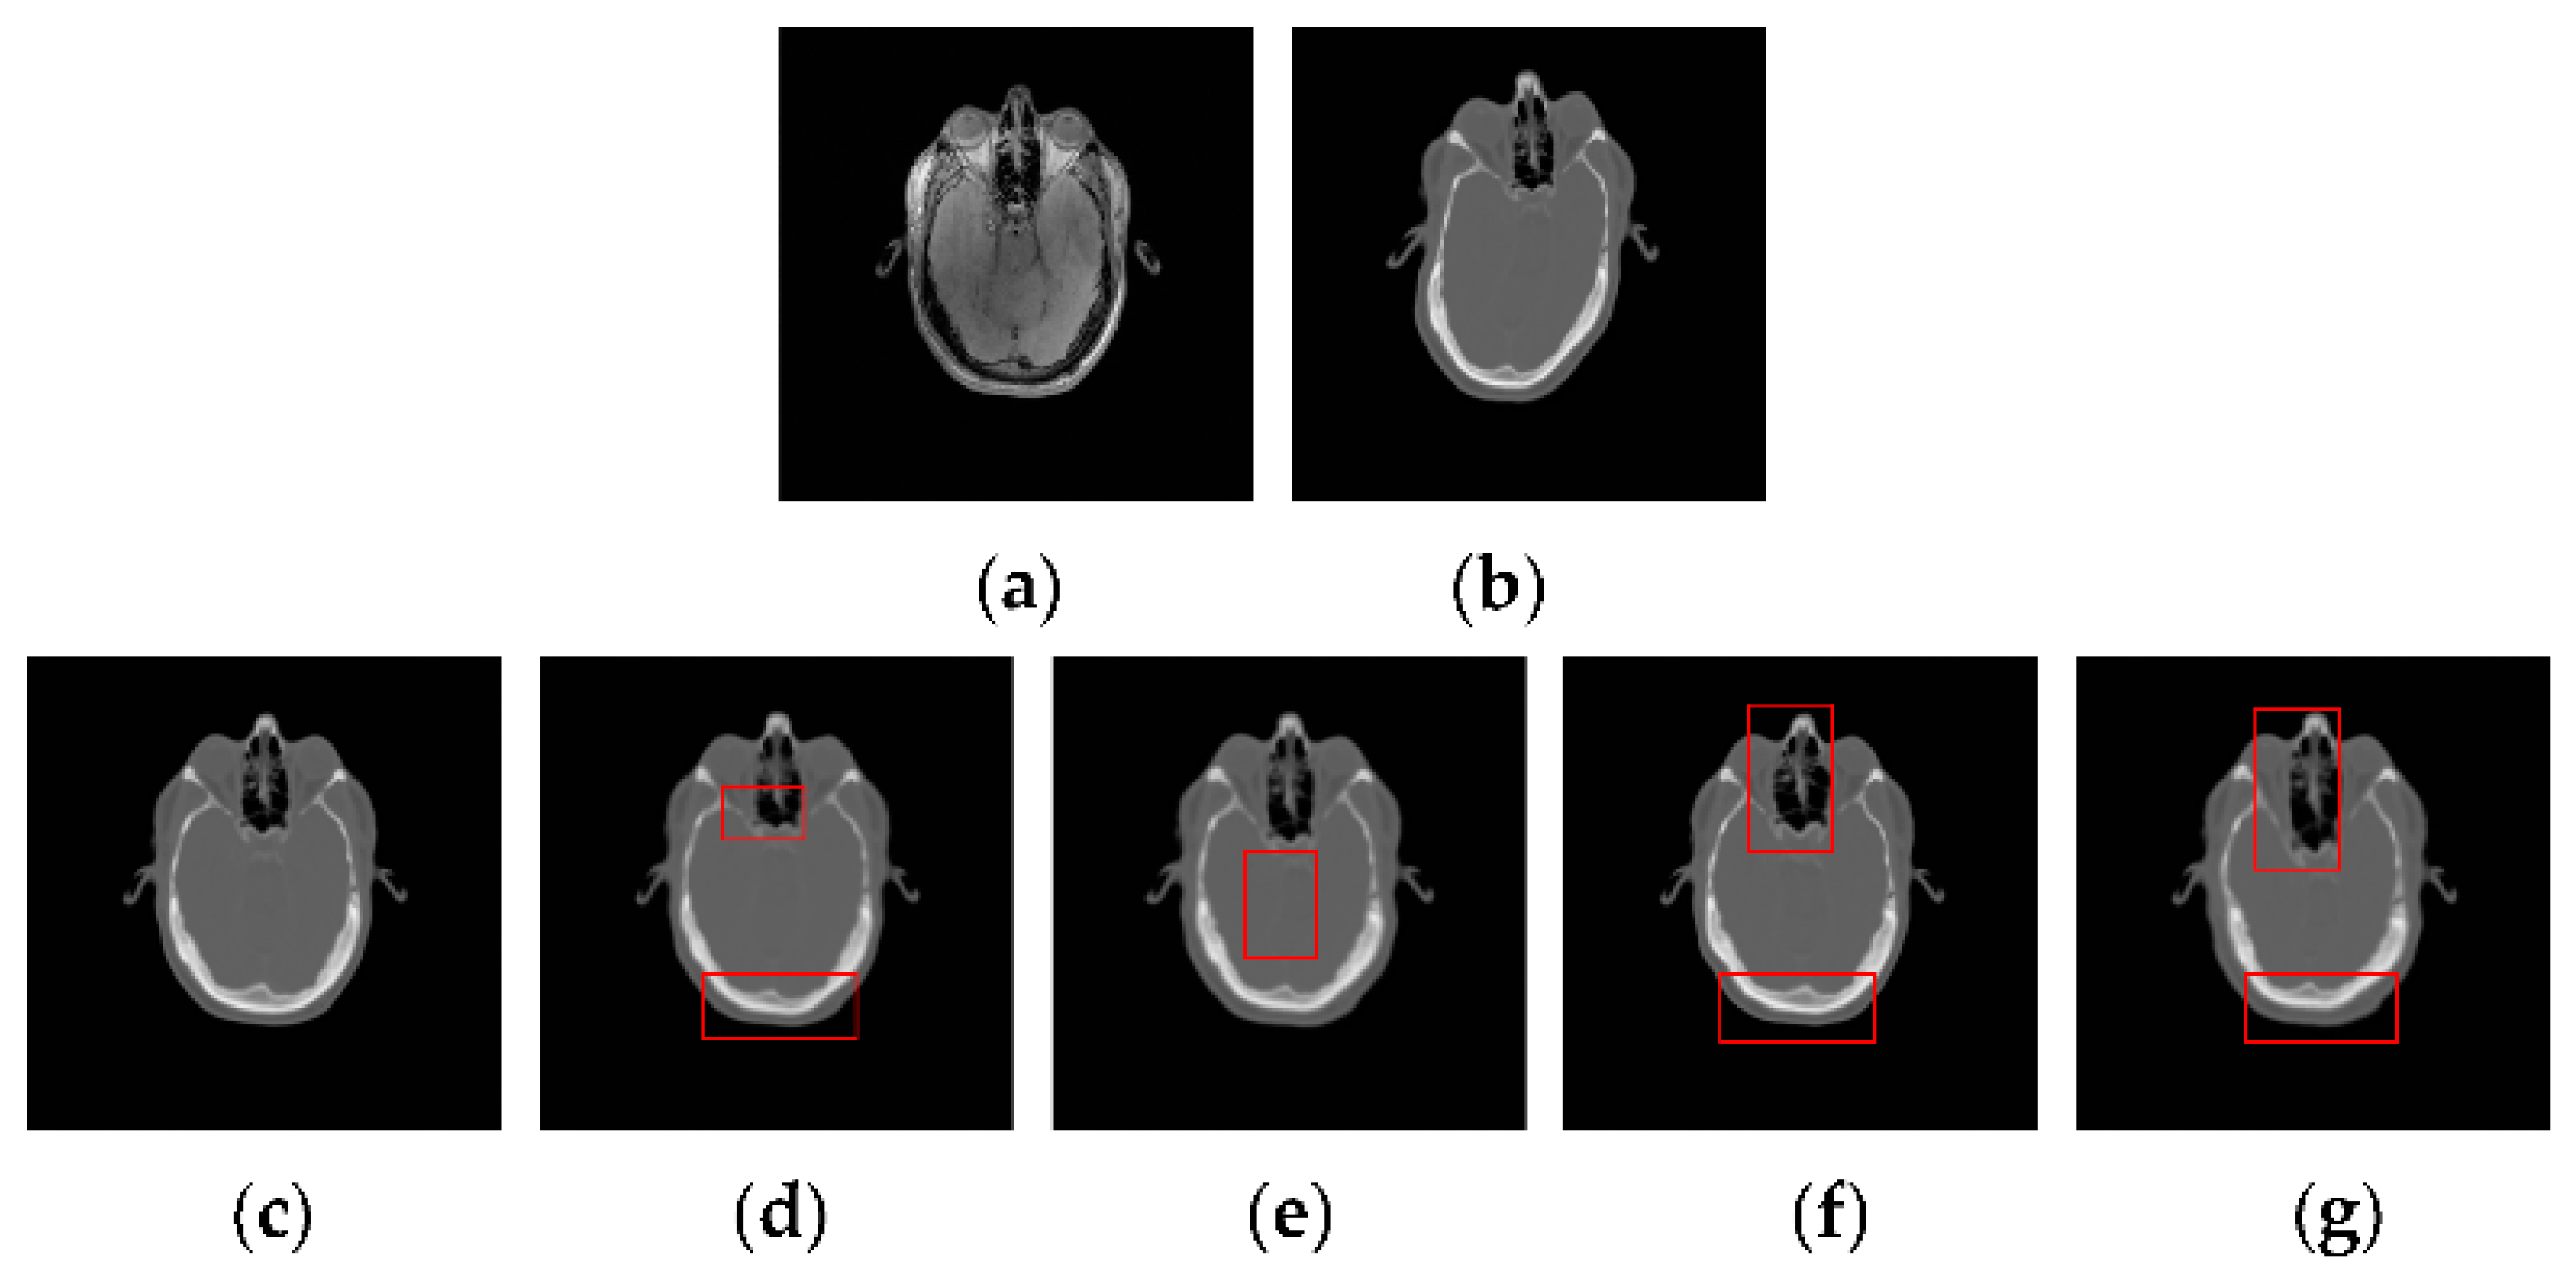

3.2.2. Test on the RIRE Dataset